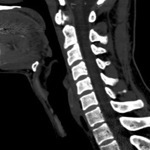

Spine

Sagittal